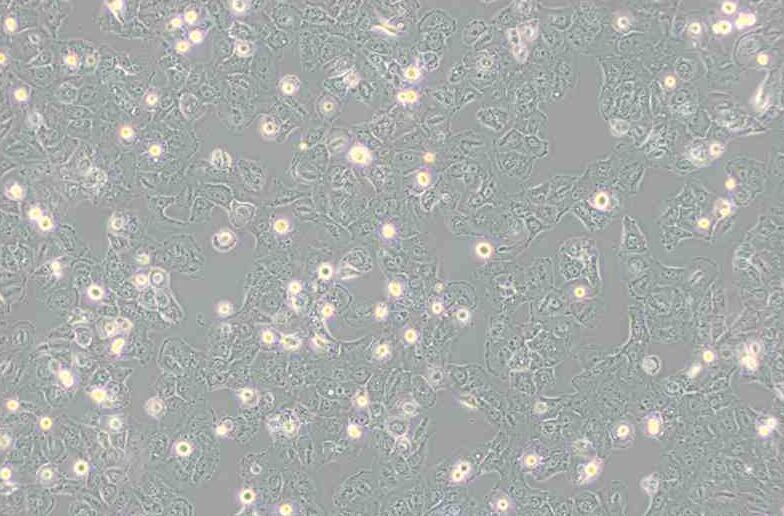

上皮细胞样

细胞形态 上皮细胞样

生长特性 贴壁细胞

贴壁细胞

细胞背景描述 Caov-3细胞是于1976年建系,源自一位54岁白人女性的卵巢腺癌组织。